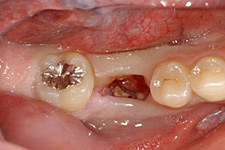

適切な条件がそろえば、歯の移植が可能です。歯の移植とは、治療することができない歯を抜いて、その場所へ本人の親知らずなどの歯を移す治療です。例えば、下のパノラマエックス線写真は18歳の男子です。右下の第一大臼歯が割れて痛みを伴って来院されました。この歯の保存できないと判断して、その歯を抜歯し,後ろにあるまだ生えていない親知らずをそこへ移植しました。移植の適切な条件とは、患者さん年齢が概ね40歳以下であること、口腔内に適切なドナー歯(主に親知らず)があること、移植歯(ドナー歯)と移植部位(受容側)の大きさが適合すること、などです。

治療前:第一大臼歯が割れてしまっていて治療することが困難です。

第一大臼歯の抜歯後2週間で移植を行いました。